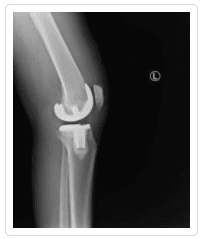

Knee X-ray Gallery

Please visit our knee x-ray gallery to see more images of knees affected by osteoarthritis.